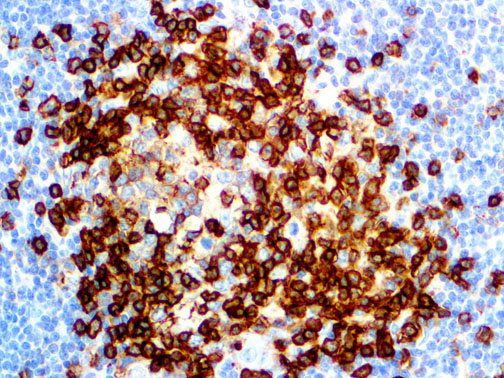

It is the ICU physician who is most likely to witness one of the deadliest manifestations of the abnormal immunological response, the cytokine storm syndrome (CSS). This response is also referred to by some as the cytokine release syndrome (CRS). CSS is characterized by continuous activation and expansion of macrophage and lymphocyte populations, which secrete large amounts of cytokines, causing the cytokine storm. This massive cytokine release is akin to hemophagocytic lymphohistiocytosis (HLH) disease, a syndrome characterized by initial unchecked and persistent activation of cytotoxic T lymphocytes and NK cells.

Clinical and laboratory manifestations of HLH include fever, enlarged liver and/or spleen, neurologic dysfunction, coagulopathy, liver dysfunction, cytopenias (i.e., low levels of erythrocytes, leukocytes, and/or platelets), hypertriglyceridemia, hyperferritinemia, hemophagocytosis, and eventually diminished NK cell activity as the immune system becomes progressively paralyzed. HLH can be familial (primary HLH) or secondary to another disease process (sHLH), such as rheumatic disease, in which it is referred to as macrophage activation syndrome (MAS, characterized by elevated ferritin).